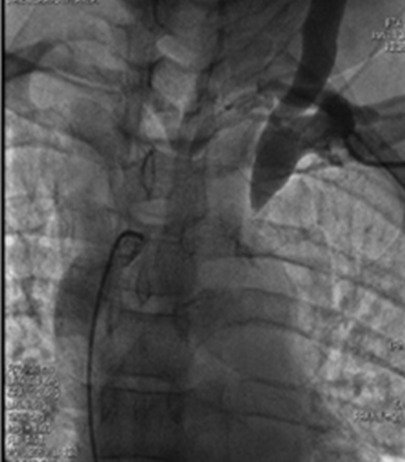

Thoracic and abdominal aortic aneurysm – TEVAR & EVAR. Aortic Dissection stenting.

Portal hypertension , bleeding and Cirrhosis, Budd Chiari management.

Outcomes observed in patients treated with image-guided, minimally invasive vascular procedures.

Results vary by patient and condition. Images are for educational purposes only.